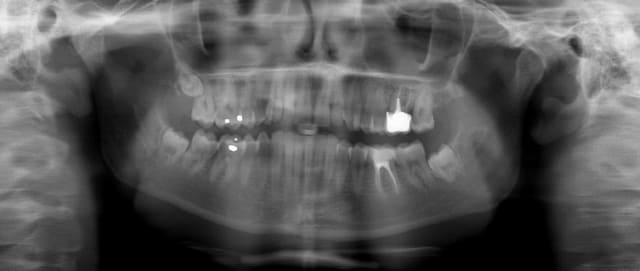

vite fait quelques copies d'écran de la Gendex CB 500 acquise il y a un an (avec le capteur de 1 ere génération)

Les modèles vendus actuellement ont un capteur optimisé pour les panos